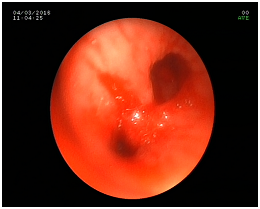

For our surprise she was rapidly fully awake but unable to wean from mechanical ventilation, following our protocol, because she was hemodynamicaly unstable with the need of high doses of norepinephrine. The angiography showed absence of obstructive coronary disease and following Mayo criteria the diagnosis of Takotsubo syndrome was set. We decided then to continue ventilation support in order to minimize the work of breath (tracheostomy) and the use of hemodynamic support (vasoconstriction) as well as checking the heart function by ECHO and the heart rhythm because of ventricular arrhythmias. Markers for tumors or neuromuscular diseases were also send without any findings. A bronchoscopy (P4) for washing-brushing was also done looking for a paraneoplastic tumor. Biopsies of the lung were taken for more investigation in order to prove theory. Nothing of the above proved unless a subclinical LID. 6 weeks later the patient remains connected to the ventilator (PS: 6/PEEP: 4), without vasopressors support and the heart systolic function normal again.

Most of the patients survive the initial acute event, with a very low rate of in-hospital mortality or complications. Even when ventricular systolic function is heavily compromised at presentation, it typically improves within the first few days and normalises within the first two months.13,14 It is not likely for the same recovered patient to experience the syndrome twice. The average ages at on set are between 58 to 75 years affecting between 1.2% and 2.2% of people in Japan and 2% to 3% in western countries (Figures 1–4).

Figure 4 P4 Bronchoscopy.